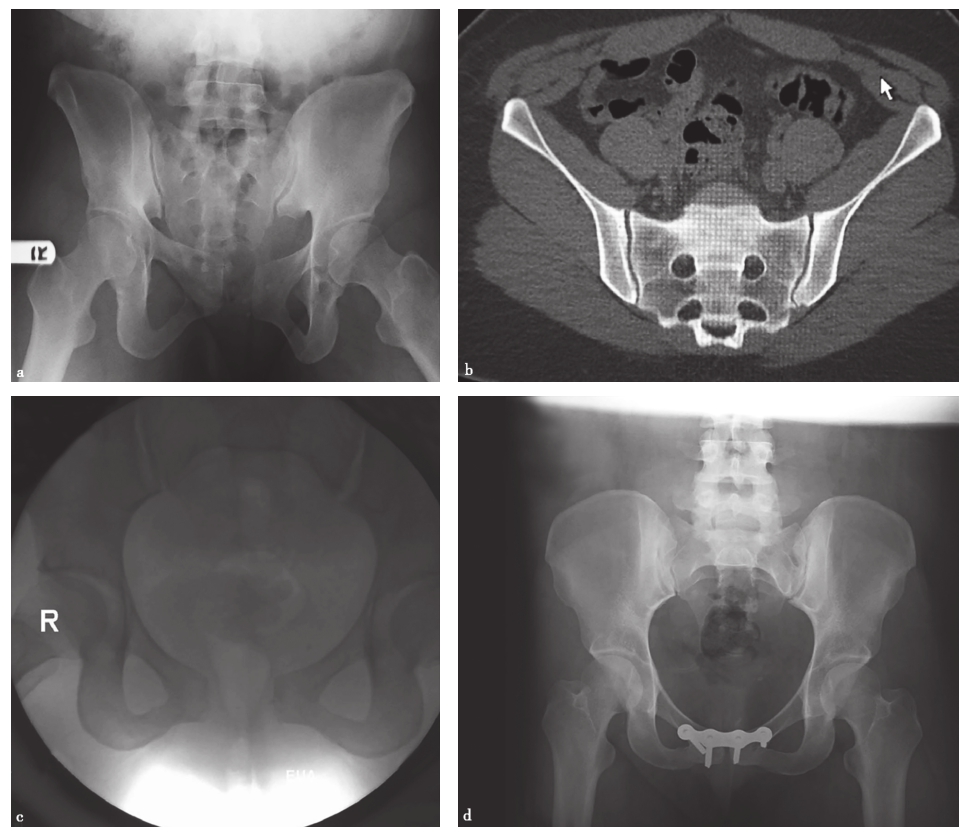

在常规的X线检查中,一些细微的失稳是无法观察到的,只有通过特殊的检查方法才能识别。Sagi等术前在麻醉下对68例骨盆后环的不完全损伤(OTA 61-B型)进行X线和CT检查。他们认为在麻醉下进行的动态应力透视检查显示,50%的前后挤压型(anteroposterior compression,APC)Ⅰ型损伤、39%的APC Ⅱ型损伤和37%的侧方挤压型(lateral compression,LC)Ⅰ型损伤都有隐性失稳(图2-12)。

图2-12 骨盆后环的不完全损伤影像

a.骨盆正位X线片示APC Ⅰ型损伤;b.CT扫描显示无明显骶髂前韧带损伤;c.外部旋转应力下透视显示为耻骨联合分离> 2.5cm的旋转不稳定型,即APC Ⅱ型损伤;d.对隐匿性APC Ⅱ型损伤的内固定术后。